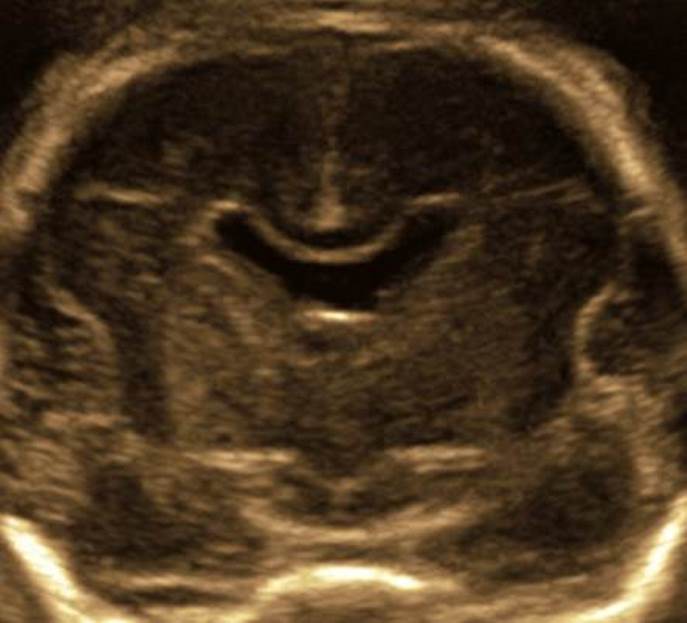

- Срок 24 недели.

- Какие особенности вы видите? Сформулируйте полный диагноз.

Ответ на вопрос 2

- В передней части передние рога разделены, но полость прозрачной перегородки отсутствует — она облитерирована. В задних отделах отсутствует прозрачная перегородка. Повышенная эхогенность и неровность контура в области герминогенного матрикса. Неровность контура бокового желудочка по всему периметру, перивентрикулярная повышенная эхогенность.

- Диагноз: мальформация коры головного мозга- перивентрикулярная нодулярная гетеротопия, частичная агенезия прозрачной перегородки, высока вероятность кровоизлияния 1 ст в области герминогенного матрикса